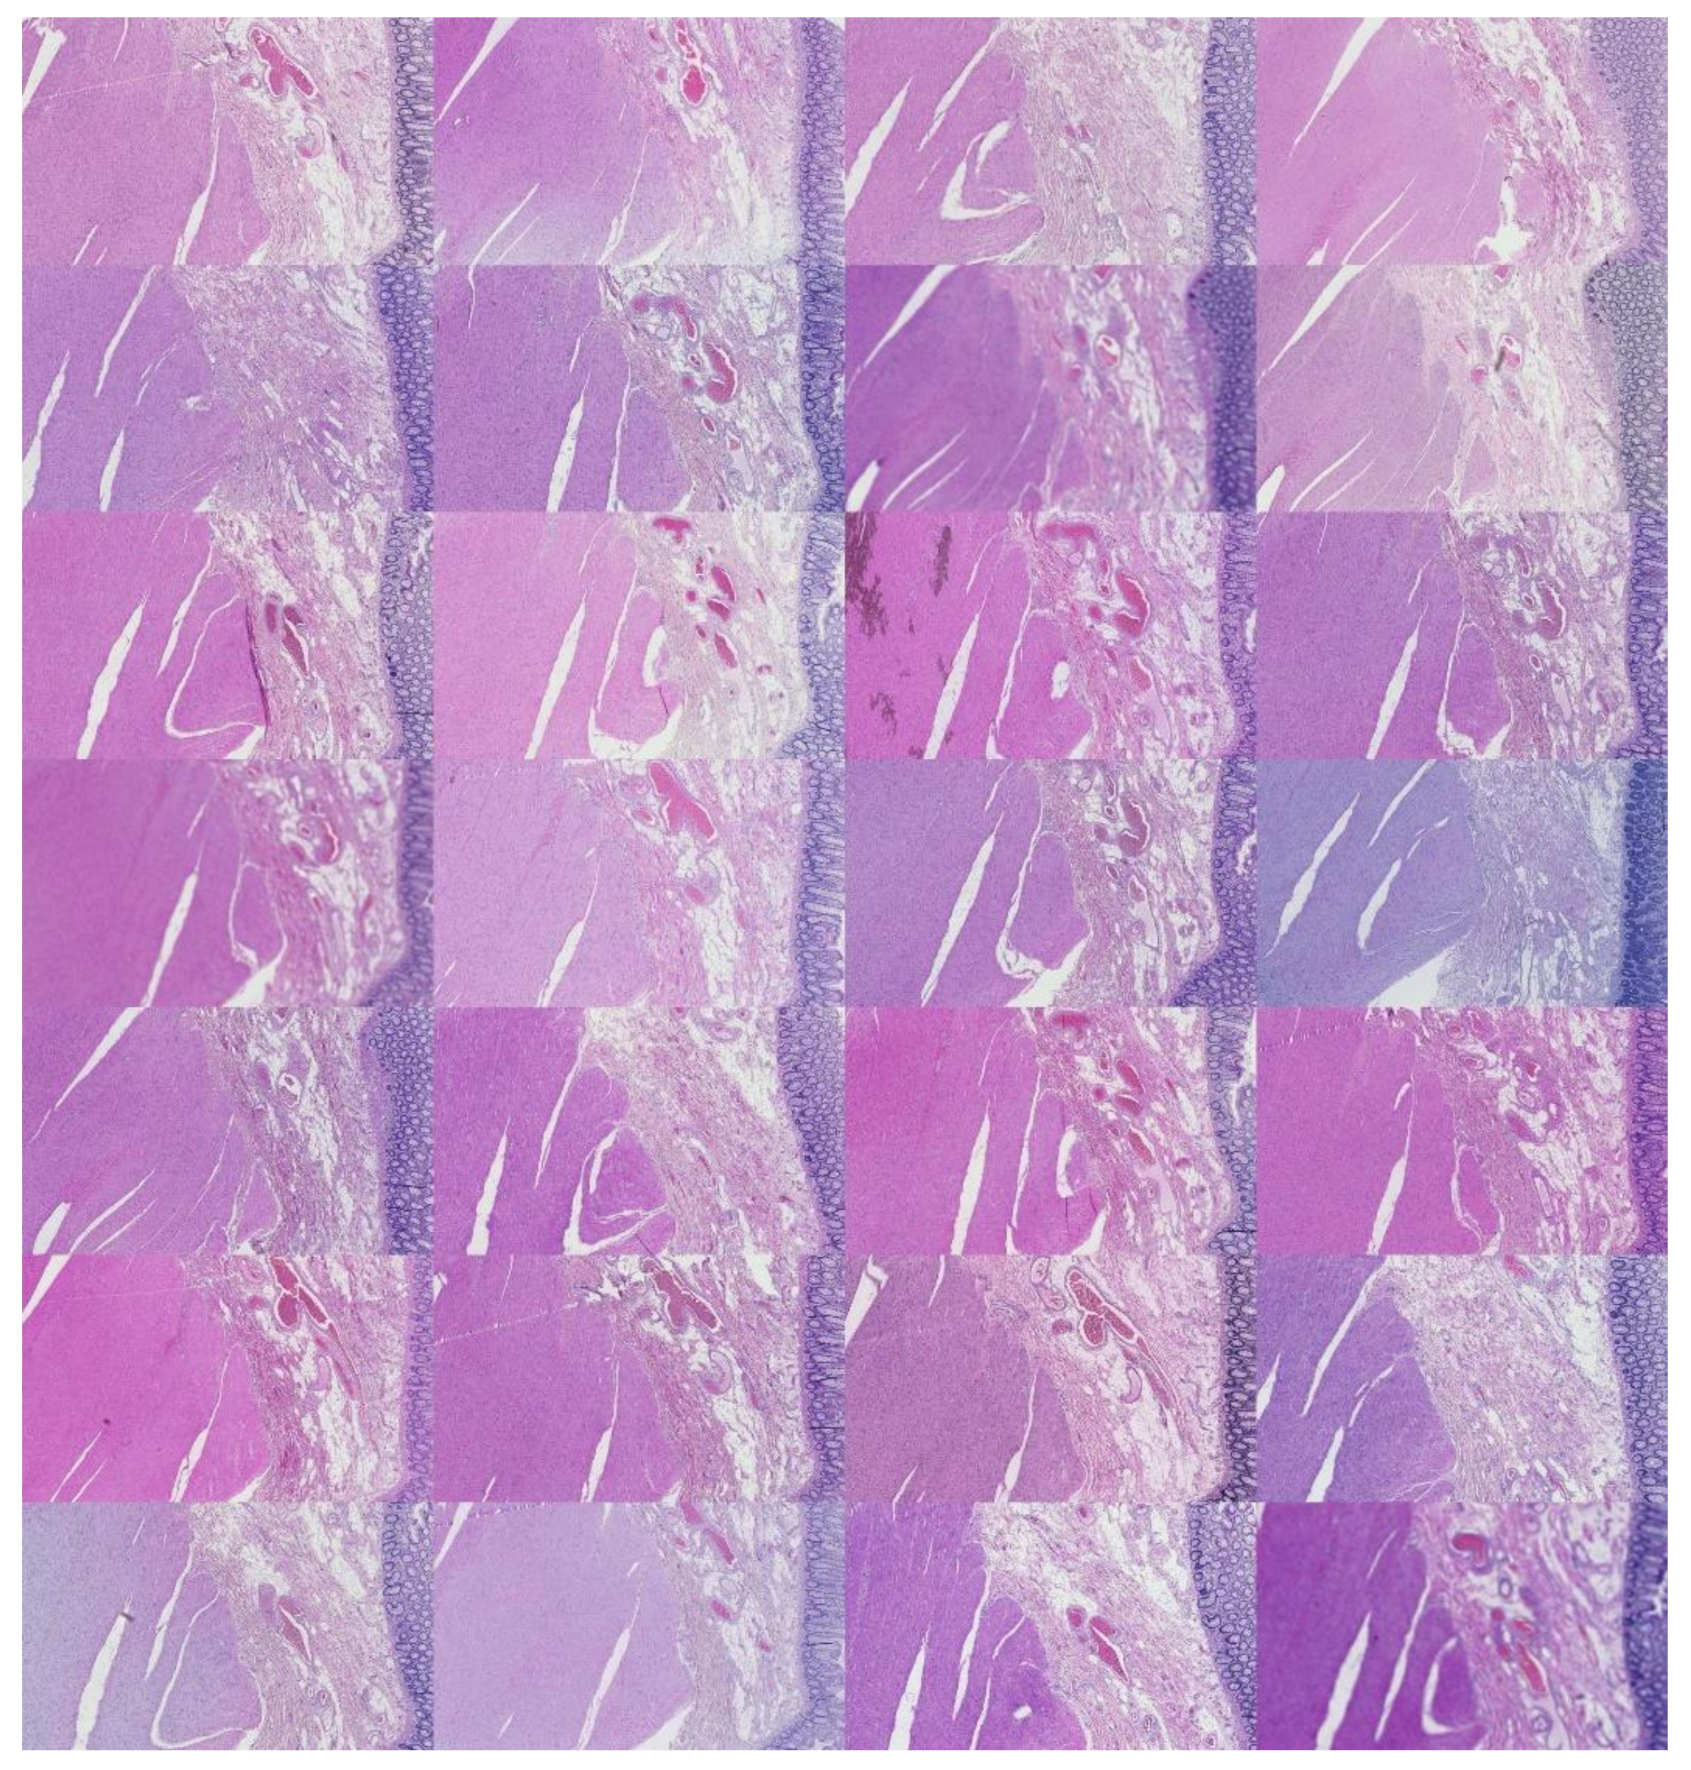

2.4.1. ROI Image Tiling

We cropped the original ROIs into 128 image tiles per ROI to conduct supervised learning. The image patches were non-overlapping and 113 × 90 pixels each in size. Consequently, this amounted to 8488 image patches distributed equally amongst 66 laboratories per tissue type. There were 25,462 tiles in total across all laboratories. The ground truth of each patch was the laboratory from which the original ROI was processed. This resulted in 66 ground truth classes, one for each laboratory containing 128 image patches. Examples are shown in Figure 7.

Figure 7.

For illustration purposes, three tiled ROIs from three laboratories (per row). The first row is kidney, the second is skin, and the last is colon.